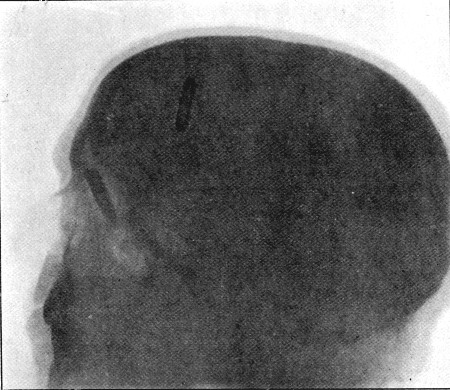

60. Skiagram of Bullet in Nasal Fossa 244

61. Diagram of Aperture of Entry into Cranium 245

62. Aperture of Entry into Frontal Bone 252